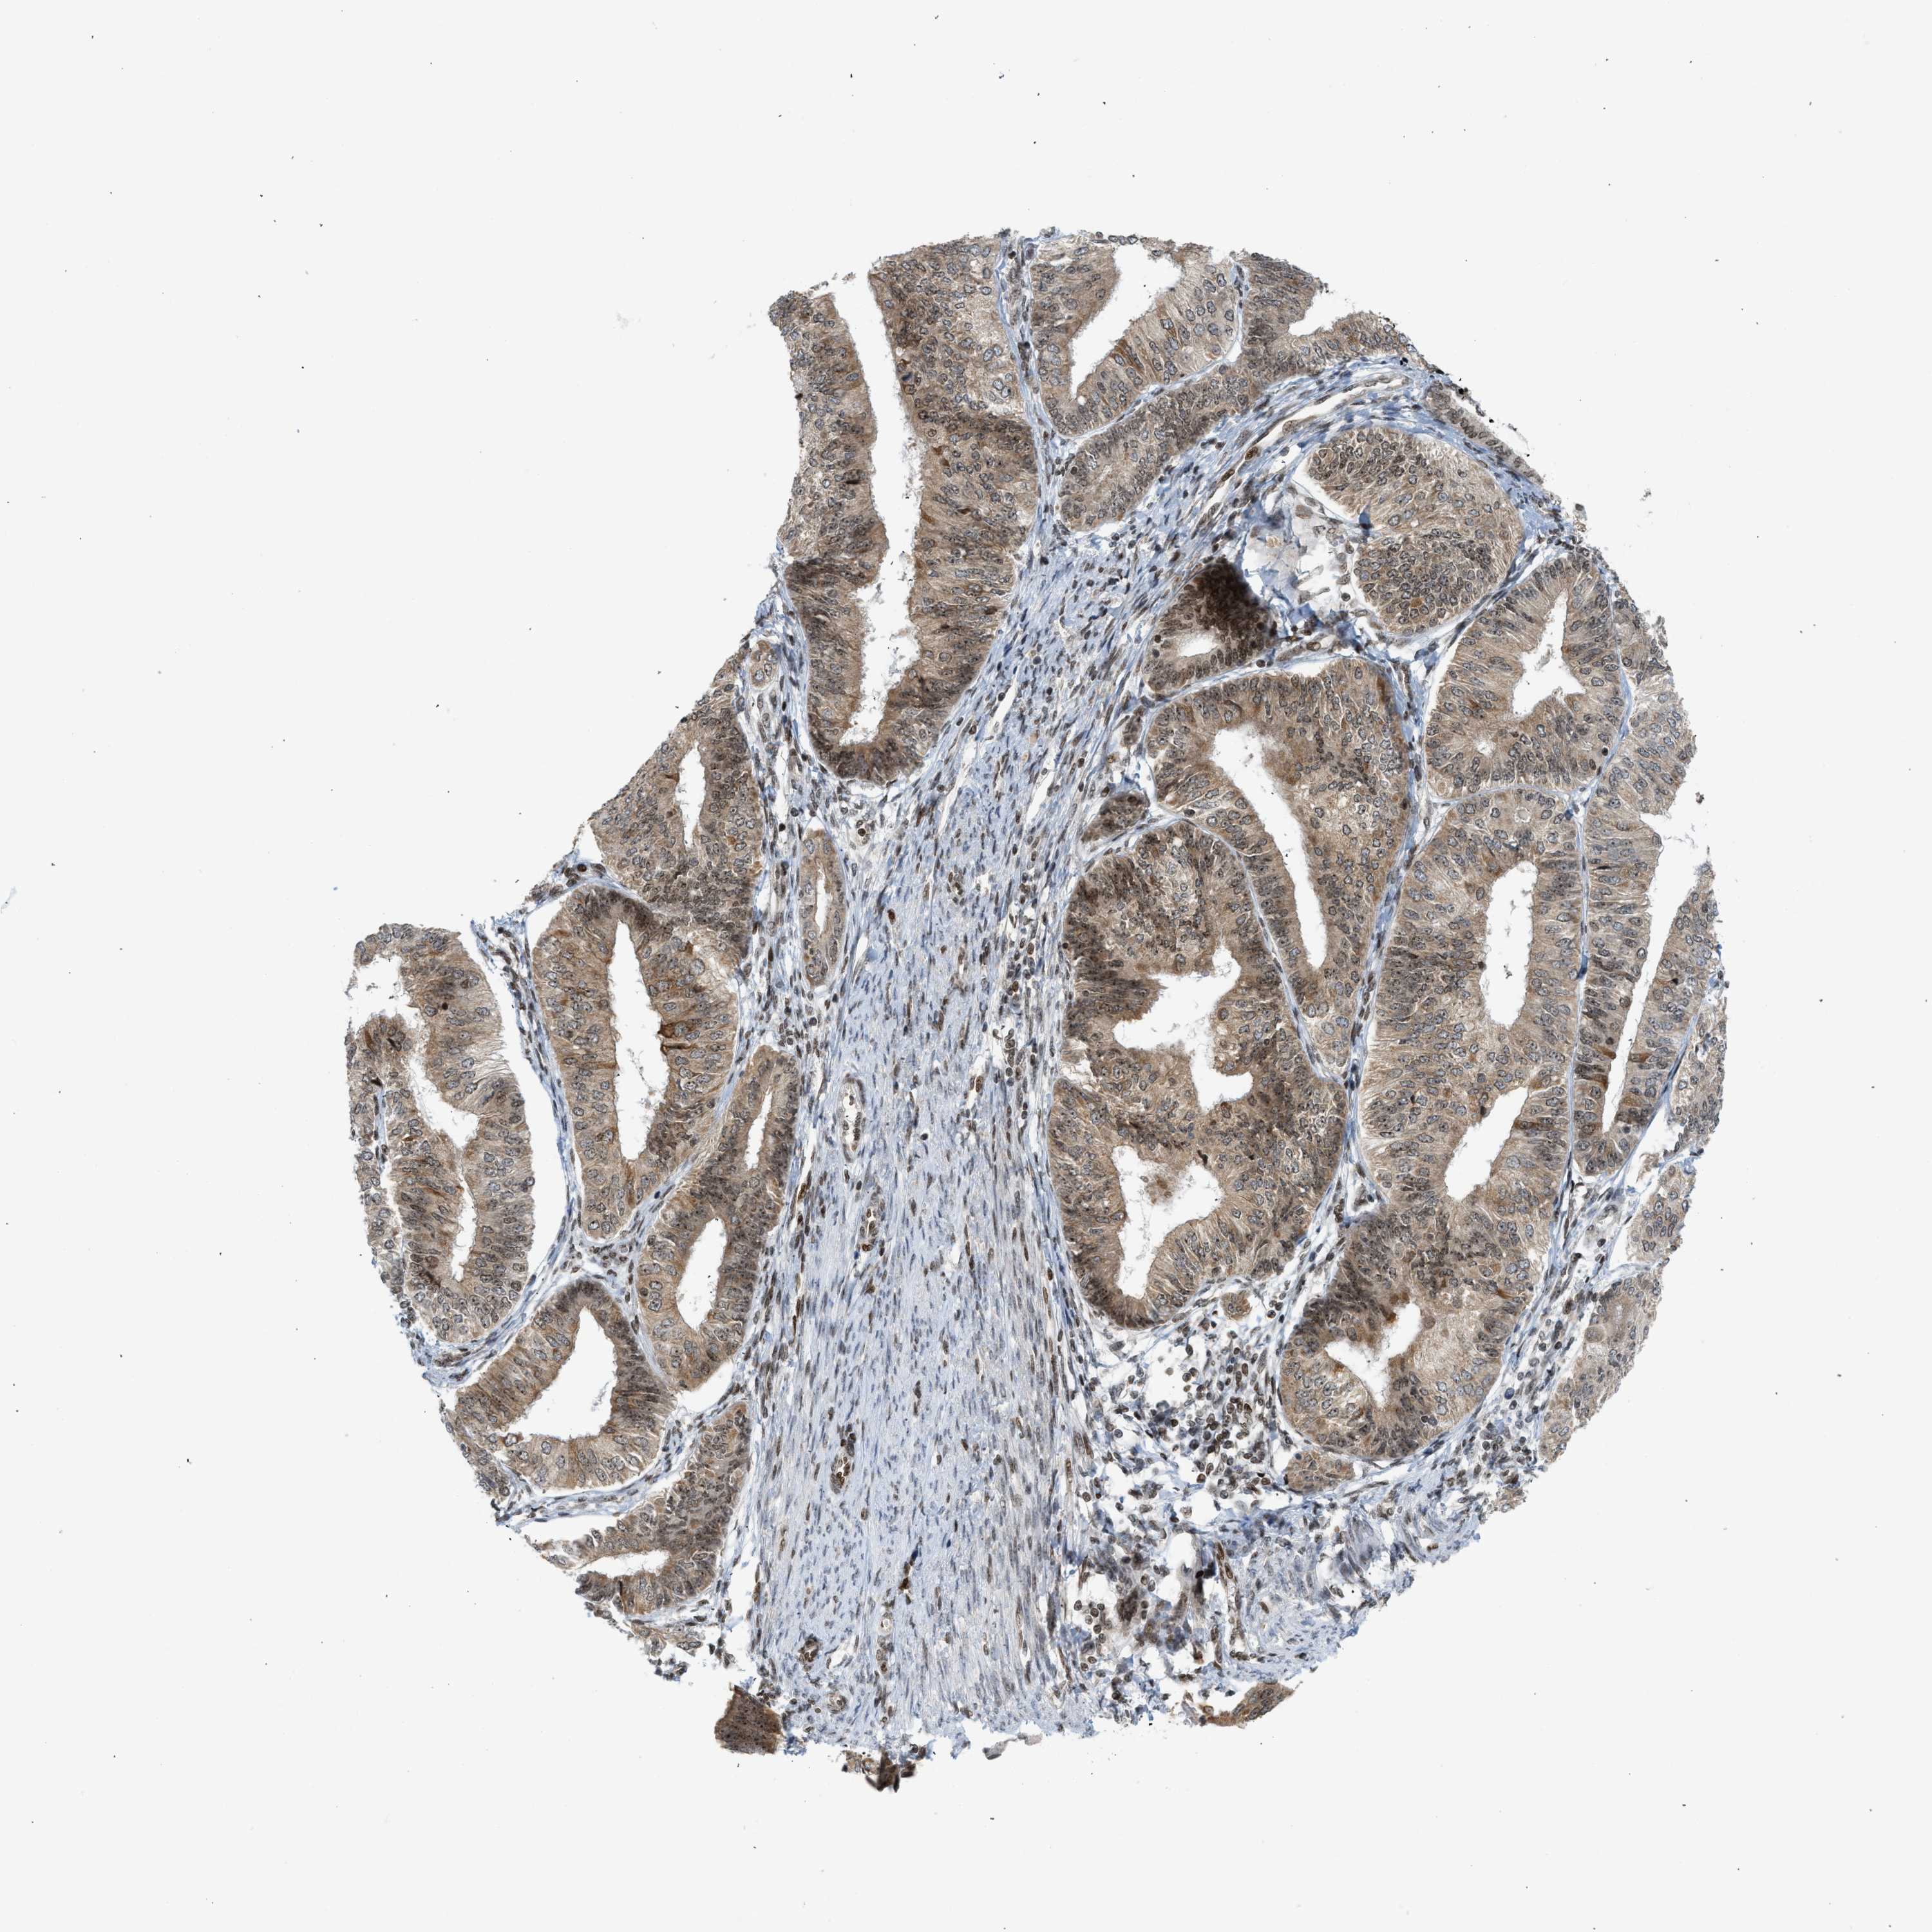

ENDOMETRIAL CANCER - Protein expressioni

A mouse-over function shows sample information and annotation data. Click on an image to view it in a full screen mode. Samples can be filtered based on level of antibody staining by selecting one or several of the following categories: high, medium, low and not detected. The assay and annotation is described here.

Note that samples used for immunohistochemistry by the Human Protein Atlas do not correspond to samples in the TCGA dataset.

Antibody stainingi

Antibody staining in the annotated cell types in the current human tissue is reported as not detected, low, medium, or high, based on conventional immunohistochemistry profiling in selected tissues. This score is based on the combination of the staining intensity and fraction of stained cells.

Each image is clickable and will lead to virtual microscopy that enables deeper exploration of all samples and also displays staining intensity scores, fraction scores and subcellular localization as well as patient and tissue information for each sample.

Antibody HPA016736

Staining

High

Medium

Low

Not detected

Intensity

Strong

Moderate

Weak

Negative

Quantity

>75%

75%-25%

<25%

None

Location

Nuclear

Cytoplasmic/membranous

Cytoplasmic/membranous,nuclear

Adenocarcinoma, NOS